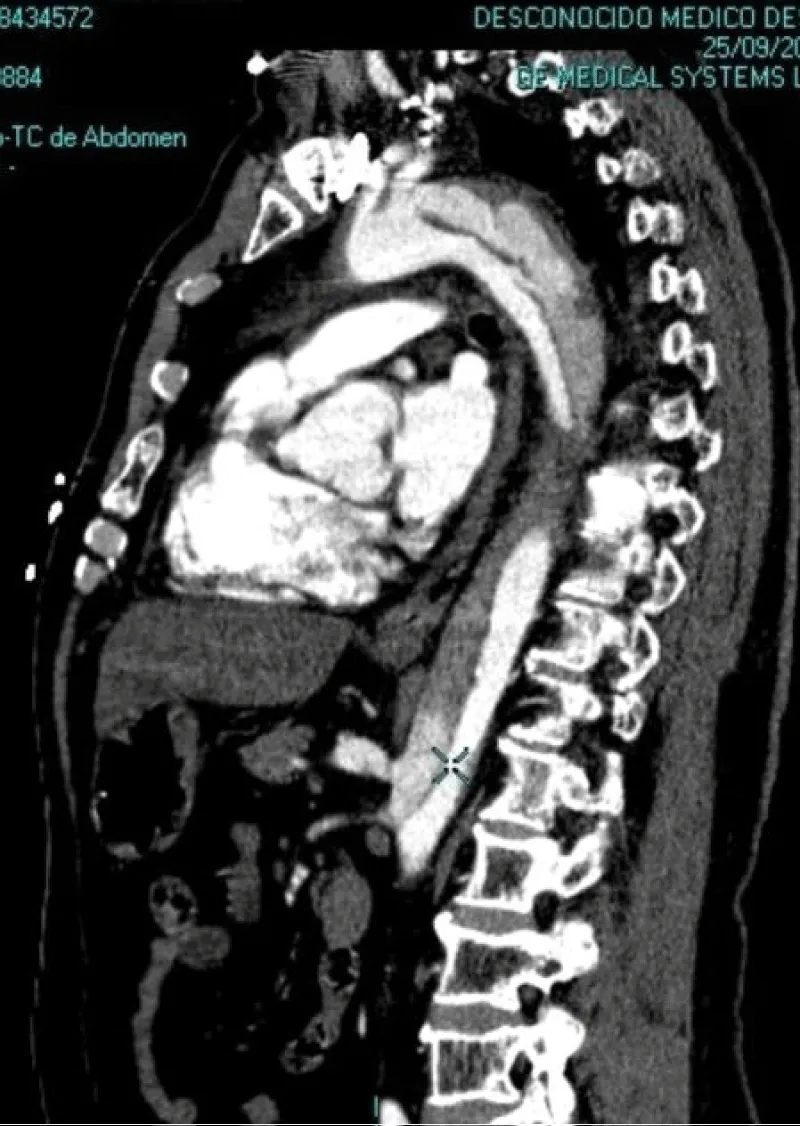

No acute ST-T abnormalities with biomarkers (troponin T and CK) repeatedly in the normal range. Normal blood count and coagulation studies. The patient is then admitted to the ICU. In the clinic of chest pain with negative electrical and enzymatic data, a CT scan is performed with intravenous contrast then unfold the existence of acute aortic syndrome Stanford type B (Figure 2). Transthoracic echocardiography was performed, showing preserved systolic function, without contractility alterations, without valvular disease but with slight left ventricular hypertrophy and slight pericardial effusion, with intimal flap distal to the left subclavian artery in the suprasternal plane.

Figure 2: Lateral CT image where it can be an observed dissection of the aortic artery, with false lumen distal to left subclavian artery to the abdominal aorta without affecting the aortic arch (Stanford type B).